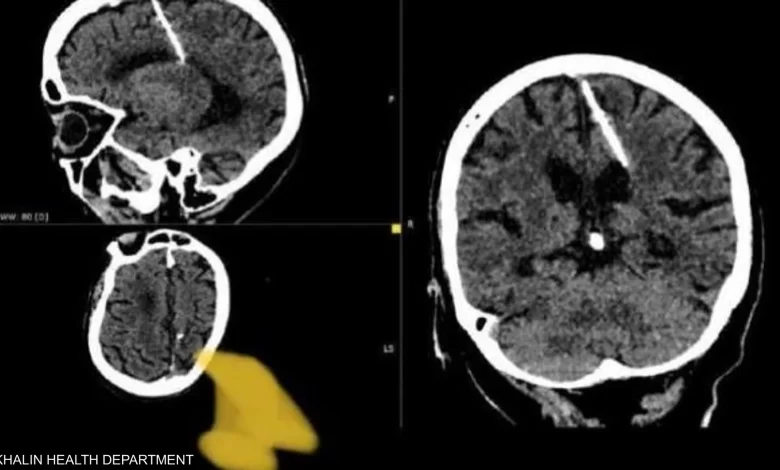

عثر أطباء خلال فحص بالتصوير المقطعي على إبرة بطول ثلاثة سنتيمترات موجودة منذ ثمانين عاماً داخل دماغ امرأة مسنّة في أقصى الشرق الروسي.

وقالت إدارة الصحة المحلية “لقد اخترقت الإبرة الفص الجداري الأيسر، لكن لم يكن لها التأثير المقصود، إذ نجت الفتاة”.